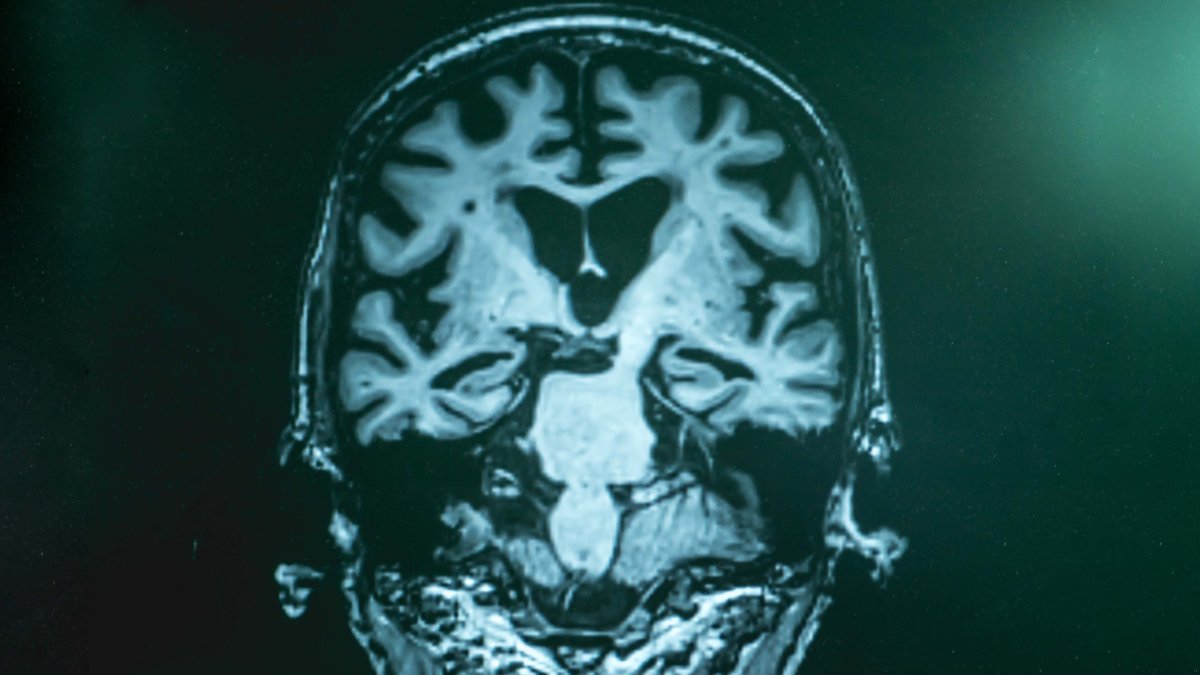

Fármaco experimental muestra eficacia contra el alzhéimer, según un estudio

TOKIO, Japón – Un nuevo ensayo clínico ha confirmado la eficacia del fármaco experimental lecanemab para ralentizar los efectos de la enfermedad de Alzheimer, aunque también ha señalado sus efectos adversos y la necesidad de estudios más prolongados. El estudio de fase tres, publicado por The New England Journal of Medicne, fue llevado a cabo…

Este es el tiempo que puede tardar un diagnóstico de Alzheimer en México, según especialista

GUADALAJARA, México- El diagnóstico para enfermedades como demencia o Alzheimer en México puede tardar entre 12 y 18 meses en los casos en los que la familia ofrece atención y seguimiento al paciente adulto mayor, afirmó este jueves la especialista en gerontología, Tania Gálvez. Durante el quinto Congreso de Alzheimer y otras demencias. Diagnósticos diferenciales,…